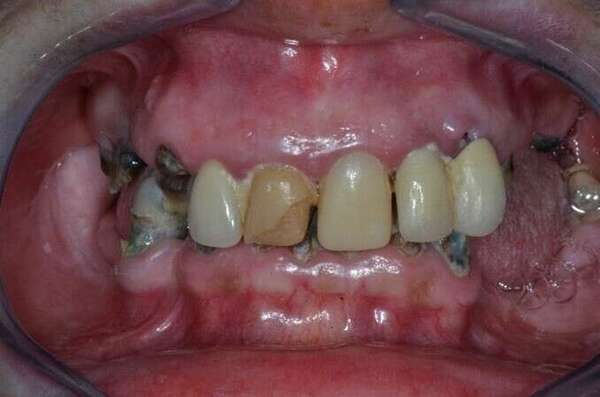

Cas d’une patiente jeune de 55 ans.